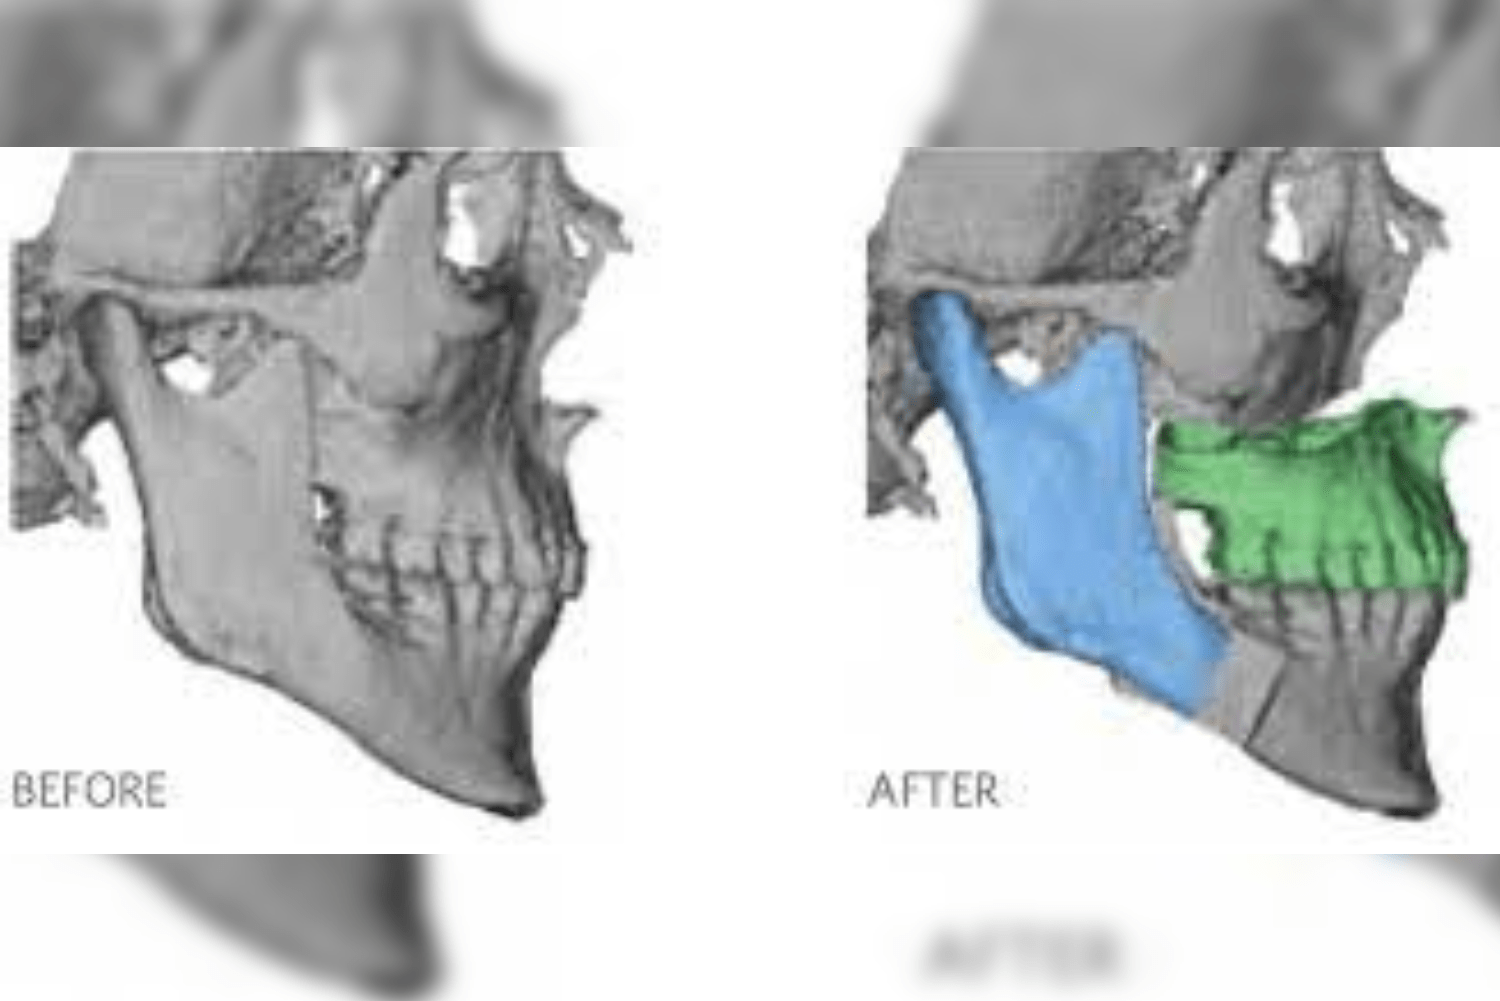

- Initial evaluation and surgical planning – when you reach out to our Dental clinic, the dentist or the surgeon will conduct a thorough examination and take scans like 3-D imaging cone beam CT scans, Digital intra-oral scans to assess your bone structure and plan the implant placement.

- Surgical placement – the surgery is performed under general anaesthesia or under local anesthesia. The type of Anesthesia depends on the patient’s and surgeon’s comfort ability. The surgeon makes small incision in the gum tissue and carefully dissect to reach the bone and places the zygomatic implants into the cheekbone. It is placed in a planned angulation and depth. In complicated cases a surgical guide is utilized to place the Implants.In many cases a temporary processes can be loaded immediately allowing you to leave the clinic with a full functional smile.

Due to improved medical facilities and thorough preoperative planning using 3-D scans with skilled surgical techniques these risks can be minimised. Choose your clinician or Surgeon wisely.